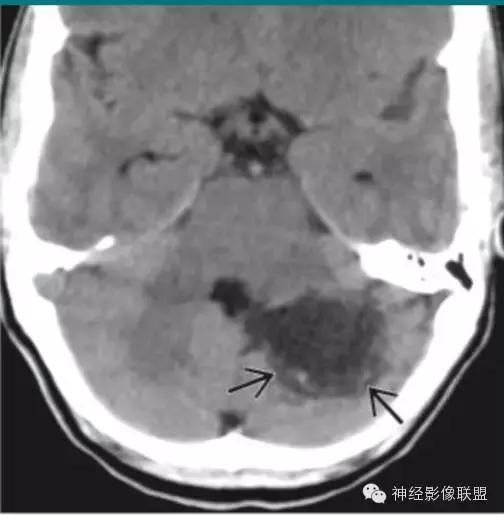

皮样囊肿破裂